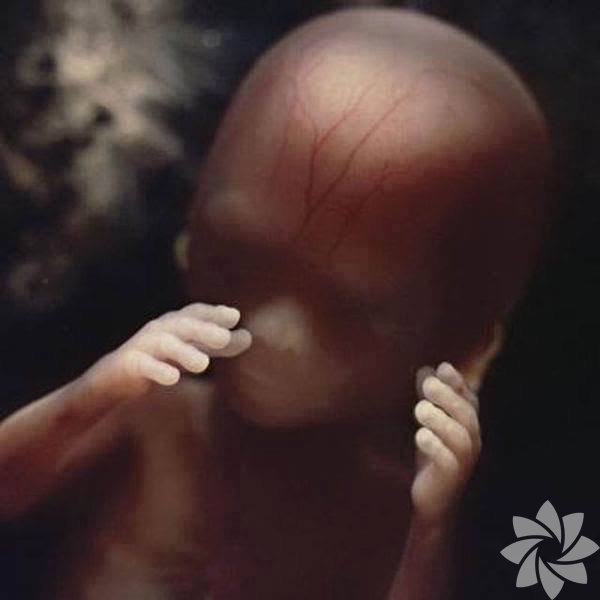

Kan damarları incecik derinin altında gözüküyor ve bacaklar hareket ediyor!

18. hafta